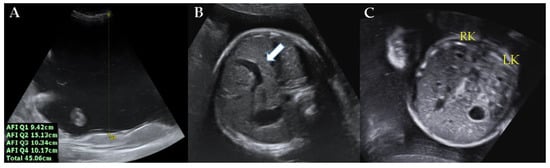

2. Case